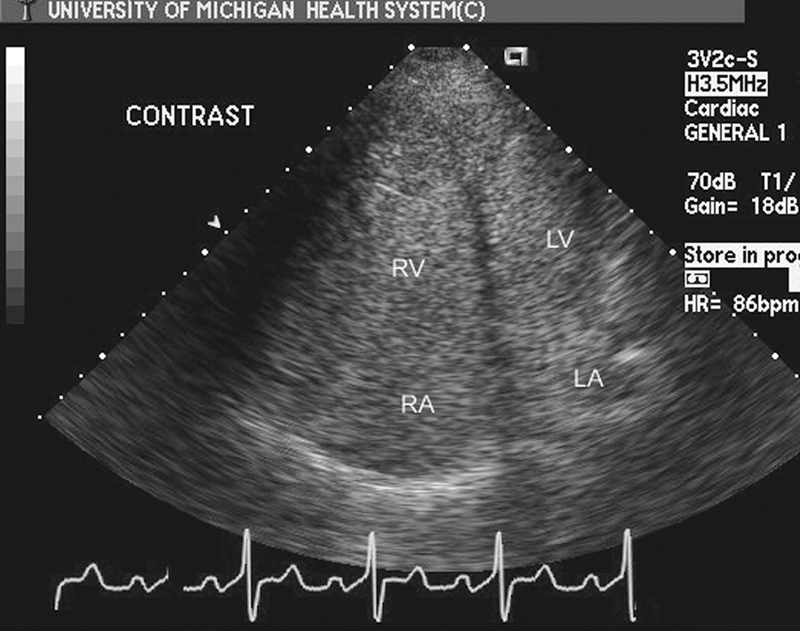

فحوصات تشخيصية لبعض امراض القلب والشرايين التاجية